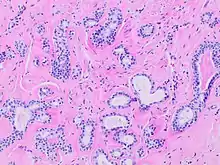

Histopathology of sclerosing adenosis of the breast.

Adenosis is any disease of a gland. The diseased gland has abnormal formation or development of glandular tissue which is sometimes tumorous.[3]